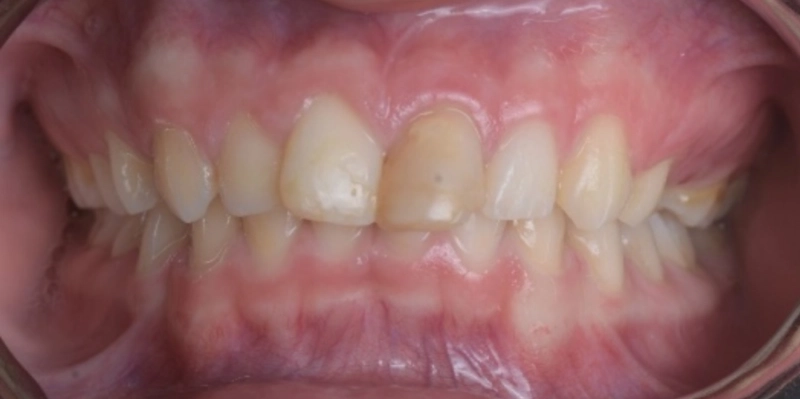

תמונות לפני ואחרי טיפול

אחרי

בסיום הטיפול התקבלה תוצאה אסתטית ותפקודית ברמה גבוהה מאוד. יחסי הסגר שופרו, הצפיפות נפתרה, הקשתות יושרו, והמראה של האזור הקדמי השתנה באופן משמעותי. מעבר ליישור השיניים, הטיפול הצליח להתמודד עם מצב מורכב של שן קדמית לאחר חבלה, תוך שמירה על זהירות ביולוגית גבוהה ותכנון זהיר של כל שלב. זהו מקרה שממחיש כיצד אורתודונטיה מותאמת אישית איננה רק בחירה במכשור מסוים, אלא היכולת לתכנן את סדר הפעולות הנכון, לשלוט בתנועת שיניים באופן סלקטיבי, להתחשב במגבלות הביולוגיות של כל שן, ולהוביל לתוצאה אסתטית מצוינת גם כאשר נקודת הפתיחה מורכבת במיוחד.